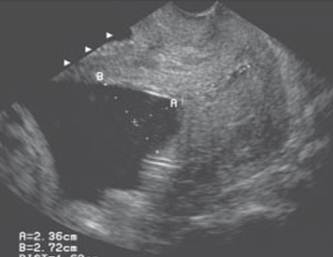

Measurement of incompetent cervix